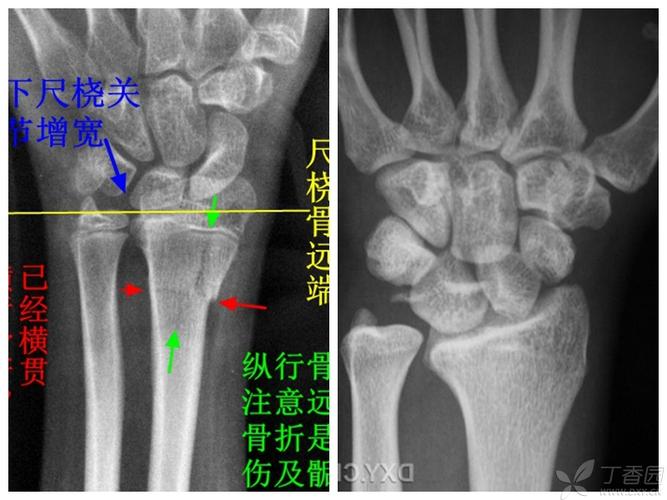

找一个园子里的正位片,对照一下尺桡骨远端的大致关系.

正常右桡骨远端骨图片

右侧桡骨远端骨折图片

右手桡骨远端骨折图片

桡骨远端骨折复位图片